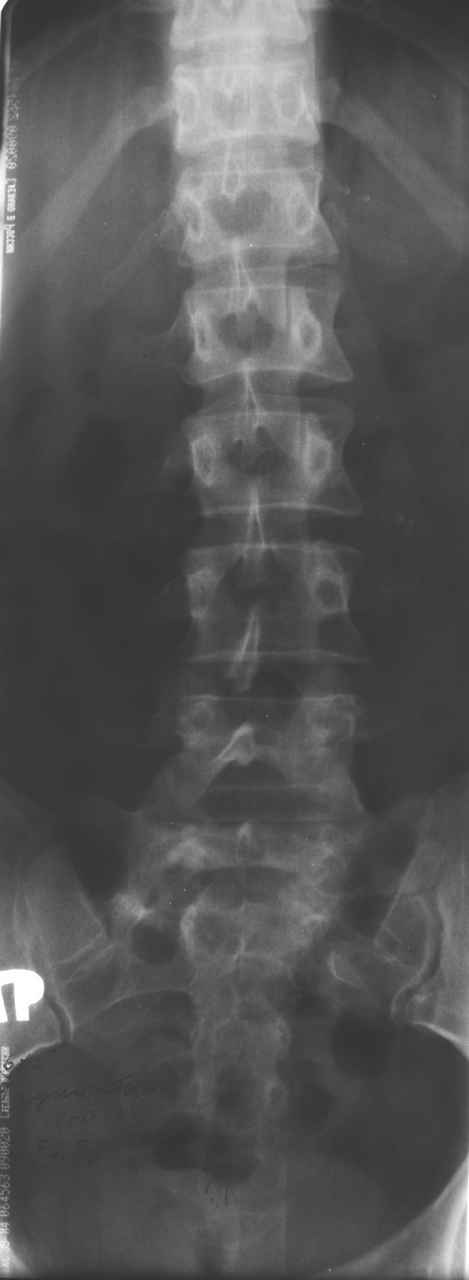

13/03/03 |  13/03/03 |  13/03/03 |  15/09/06 |  15/09/06 |  07/03/07 |  07/03/07 |  19/12/06 | К нам в клинику поступила пациентка 30 лет с диагнозом: Постравматическая ротационная стабильная деформация тазового кольца. Относительное укорочение левой н\конечности на 1 см. Левосторонний компенсаторный сколиоз 2 ст. Болевой синдром. травма автодорожная в январе 2003г. Пассажирка переднего сидения ваз 2109. лечились положением по Волковичу. С марта 2003 года жалуется на боли в тазу, ппояснице усиливающиеся при движении.В настоящее время жалобы на боли в области крестца, КПС больше слева, в пояснично-крестцовом отделе позвоночника. неприятные ощущения, щелчок при выпрямлении правого тазобедренного сустава из положения полного сгибания. боли в тазу появляются при ходьбе ч\з 100 м, так же при вставании из положения сидя, после сидения в течении 2-3 часов. при ходьбе более 100 м появпяется зябкость стоп больше справа. ходит при помощи трости в правой или в левой руке. без трости боли появляются сразу после начала ходьбы. пальпация болезненна в паравертебральных точках средне-грудного и пояснично-крестцового отделов позвоночника, КПС с обеих сторон. Объем движений в тазобедренных суставах полный.правый КПС заблокирован. симптомы натяжения с обеих сторон отрицательны.С 2003г. лечится консервативно, получала ЛФК, массаж, физиолечение - без эффекта. в 2005г. лечилась в санатории с ортопедическим уклоном, получала плавание в минеральной воде, магнитотерапия, массаж, ЛФК. отмечала умеренное улучшение в течении 2 недель.Вопросы:надо ли оперировать, т.е. устранять относительное укорочение левой н\конечности и как?Если не оперировать, то как лечить консервативно?Р-граммы, КТ прилогаются.

Проблема Вашей пациентки находится на границе интересов специальностей ортопедия (вертебралогия) и неврология (нейрохирургия), вероятно, поэтому так мало откликов на ваше обращение. Представленные рентгенограммы не все информативны (особенно спондилограммы от сентября 2006 года). Вероятно, необходимы дополнительные методы исследования к.т. МТГ, ЯМРТ, миелография.

Уважаемый Алексей. Описанные Вами клинические проявления указывают на нестабильность левого крестцово-подвздошного сочленения. Такие больные встречаются не редко (за последние 6мес.в нашей клинике оперировано 3 больных со сроками давности от 6мес. до 1 года). К сожалению рентгенологически их трудно обьективизировать. На КТ это проявляется артрозом и костными разрастаниями КПС. В Вашем случае рентгенограммы и представленные томограммы ничего не дали. Можно попробовать посмотреть связочный аппарат КПС на МРТ хотя не уверен что Вы получите окончательный ответ. Если Вы будете убеждены в этом диагнозе то выход один костно-пластический артродез левого крестцово-подвздошного сочленения с фиксацией канюлированными шурупами. Заманчиво конечно и устранить ротационное смещение половины таза, но это на Ваше усмотрение.

Уважаемый Максим. Снимки от 7.03.07 и есть функциональные, т.е. стоя на правой, и левой ноге.